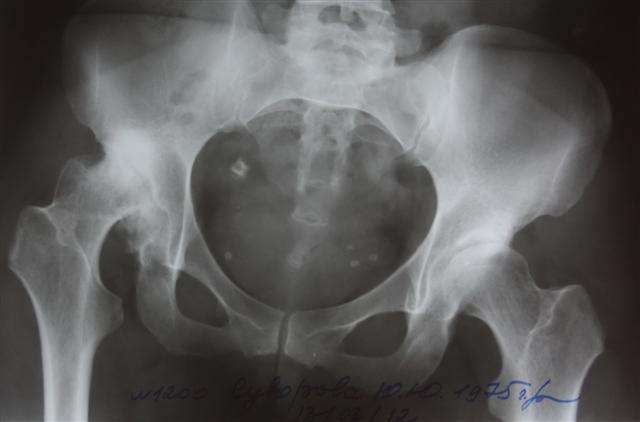

На сегодняшний день общепризнано, что эндопротезирование тазобедренного и коленного суставов является единственным эффективным методом лечения при разрушении суставного хряща и позволяет избавит пациента от боли и вернуть его к активной жизни. В мире ежегодно выполняется более полутора миллионов таких операций. Современные эндопротезы служат десятки лет и позволяют жить полноценной жизнью даже молодым и активным пациентам, а в случае, если эндопротез всё же износился, его можно заменить на более сложный и продолжать пользоваться всеми благами жизни.

В последние годы мы активно занимаемся проблемой эндопротезирования тазобедренного сустава у молодых пациентов, в том числе при врождённой патологии (дисплазии) используя при этом новейшие высококачественные долговечные эндопротезы.